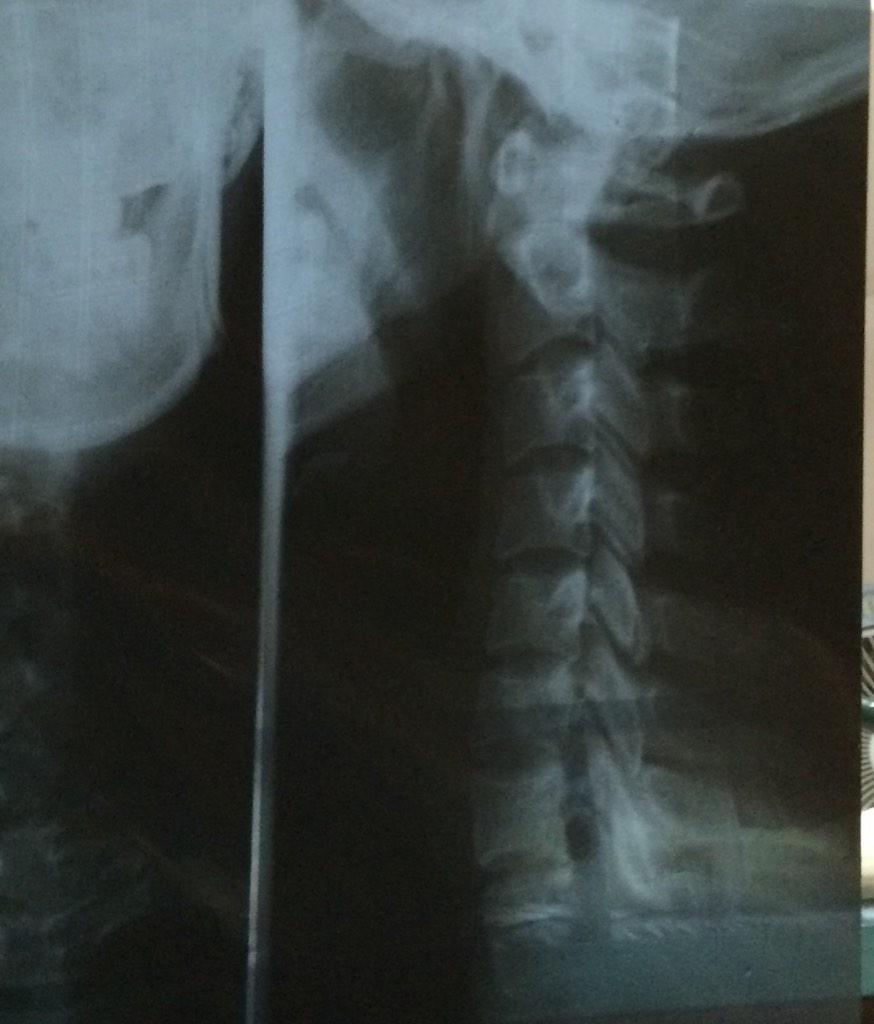

My poor neck, look what I've done to you!

@avantgame Oh thanks! It's the cervical curve.. Healthy neck has a beautiful curve but mine is almost straight

. It's due to some bad habits

@avantgame ..like sitting in front of the computer for too long, wrong pillow.. It's not very serious but heal takes time. I need to quit..

@avantgame ..some bad habits and strengthen neck muscles through exercise!